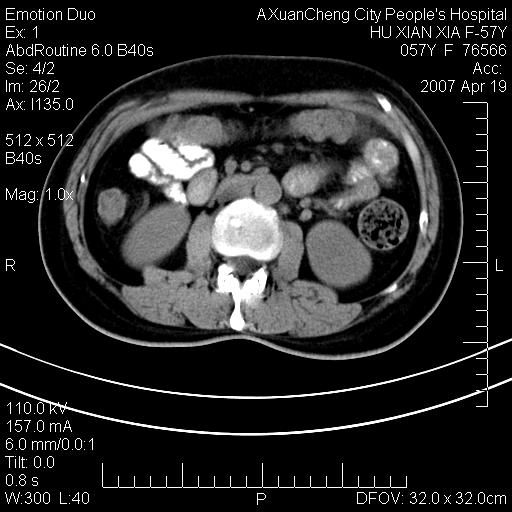

标题: CT7778:[原创]F,57Y腹痛待查,胸片提示肺部占位,应当很典型 [打印本页]

标题: CT7778:[原创]F,57Y腹痛待查,胸片提示肺部占位,应当很典型

胸片提示肺部占位

考虑:1、双侧肾上腺占位.2、肝左叶内侧段不规则低密度灶,建议强化扫描.

忽略了,只以为急腹症,应该支持肺癌肾上腺转移,肺癌患者20-30%发生肾上腺转移

双侧肾上腺增大,有分叶,密度均匀,考虑转移建议查原发灶

1.双侧肾上腺占位,转移首先考虑。

2.肝硬化,门静脉高压;肝左叶内侧段病灶建议增强。

3.12指肠水平段狭窄,建议行低张12指肠造影。

双侧肾上腺结节样肿块,结合肺部肿块,考虑肺癌肾上腺转移。

双侧肾上腺及腹膜后淋巴结增大,结合胸片提示肺部占位,考虑肺癌双侧肾上腺及腹膜后淋巴结转移.